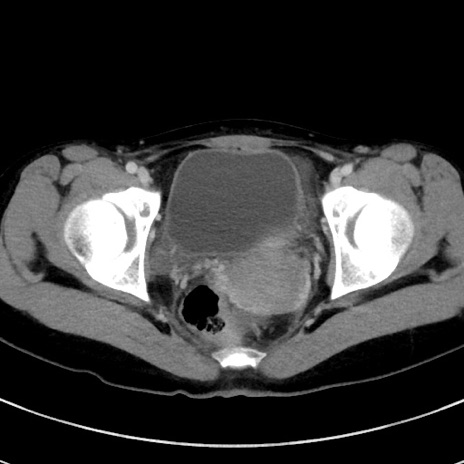

症例17(横断像)

【症例】20歳代女性

【主訴】嘔吐、下腹部痛

【現病歴】昨日夕食後に嘔吐し下腹部痛が出現。本日になっても嘔吐持続し改善しないため来院。

【身体所見】意識清明、BT 37.2℃、BP 108/67mmHg、腹部:平坦、やや硬、下腹部正中から右にかけて圧痛あり、反跳痛軽度あり、tapping pain(+)。

【データ】WBC 13600、CRP 14.94